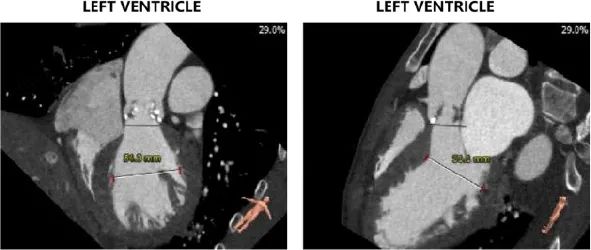

主动脉根部评估:

左冠开口高度12.0mm,右冠开口高度17.8mm,左冠高度较低,根据瓦氏窦内径和瓣叶长度综合判断,左冠存在较高堵塞风险;左室腔增大,心室壁未见明显增厚。